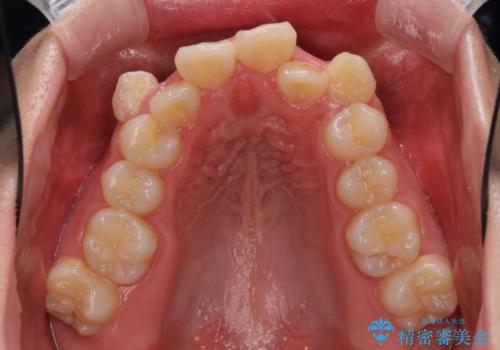

著しい叢生と顎骨のズレ ワイヤー装置による抜歯矯正

- 前歯の著しい叢生や八重歯を気にして来院された患者様です。

上下の顎がずれており、上下の正中は歯1本分の差がありました。

上下左右の小臼歯4本を抜歯し、極力正中を合わせるように矯正治療を始めていくこととしました。

咬み合わせの乱れが著しく、治療途中で一部反対咬合となってしまいました。

アンカーなどをうまく使用して、3年の期間を要してきれいに仕上げることができました。